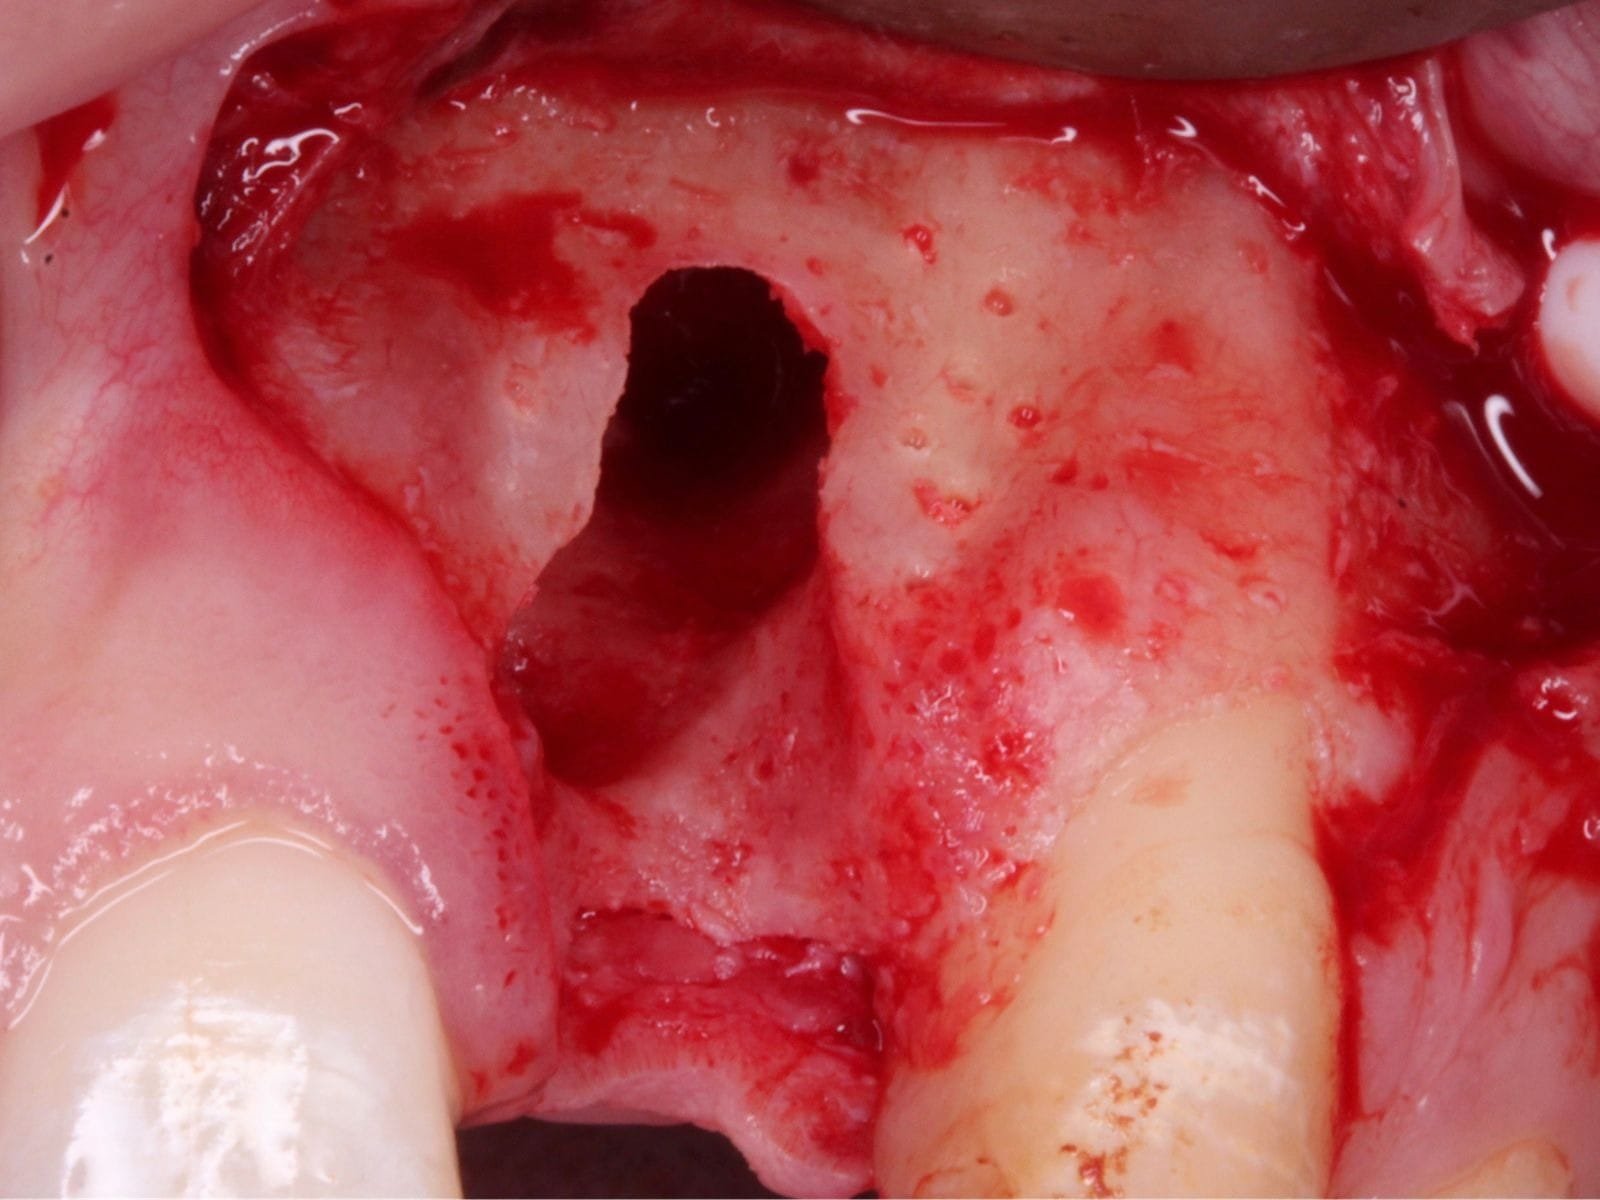

• Comprehensive case assessment and treatment planning for periodontal and peri-implant soft tissue defects

• Grafting indications for teeth and implants, particularly addressing recession and mucogingival defects

• Understand the principles of graft harvesting and management of the recipient and donor sites

• Practical application of site augmentation, including graft harvesting and managing recipient and donor sites - Use of Ossix Bone, Ossix Plus and Ossix Volumax

• Recognise, manage and prevent complications associated with soft tissue grafting

This course will teach you the fundamentals of soft and hard tissue grafting. Beginning with a brief revision of the periodontium, you will then learn how to identify patients who would benefit from such surgeries, as well as safe and effective ways to manage them. This includes suture technique and flap design, soft and hard tissue graft materials with specifications on the qualities and handling of each, and post-procedural management. Medico-legal advice and managing complications will also be discussed to help you gain a comprehensive view of this field.